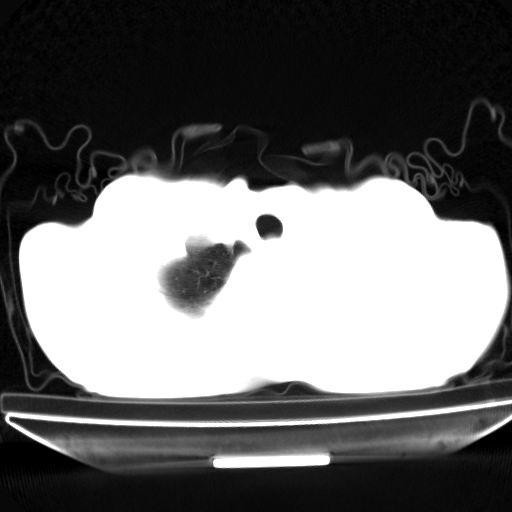

以下是引用杀毒软件在2009-4-28 17:58:00的发言:[br]考虑----左肺慢性肺脓肿形成继发上叶含气不良---抗炎后复查---待排肿瘤所致[br][br][本贴已被 杀毒软件 于 2009-4-28 18:01:26 修改过]